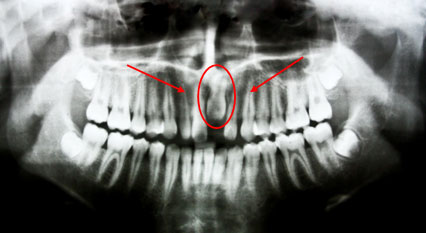

*This is a panoramic x–ray of an eight–year old patient with odontoma. Odontoma was surgically removed and tooth was orthodontically pulled out.